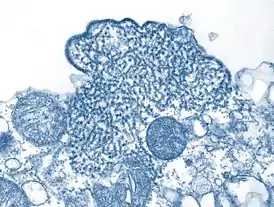

Вирус Нипах[3][4] (англ. Nipah henipavirus, ранее Nipah virus) — вид вирусов, вызывающий тяжёлую болезнь, для которой характерны воспаление мозга (энцефалит) или респираторные заболевания. Вирус Нипах тесно связан с вирусом Хендра (Hendra henipavirus) — оба вида принадлежат к роду Henipavirus из семейства парамиксовирусов (Paramyxoviridae). Природным носителем обоих вирусов являются плодоядные представители семейства крылановых (Pteropodidae).